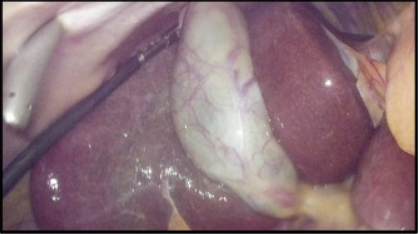

Dr. Navin Wishard has an extensive experience in Laparoscopic Surgery including Laparoscopic Cholecystectomy